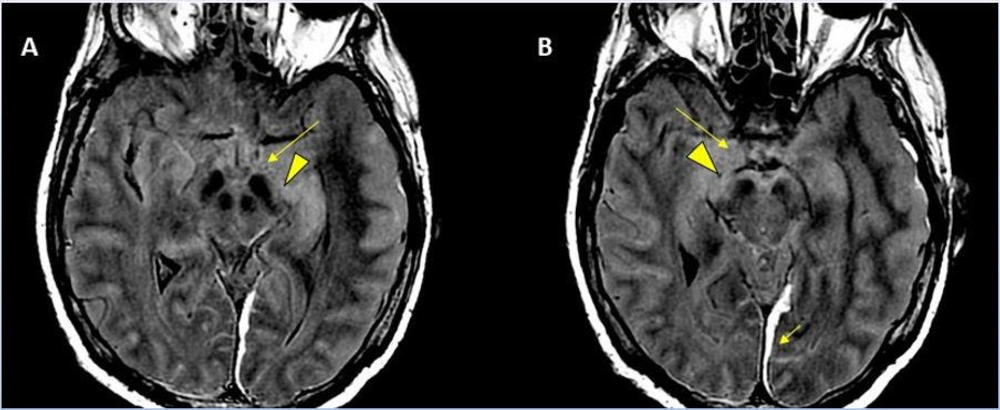

Figure 1. Stroke seen in a 41-year-old male patient with COVID-19 infection.

Figure 2. Acute anterior cerebral artery/middle cerebral artery watershed infarction seen in a 47-year-old male patient who presented with COVID-19 pneumonia. Watershed infarctions occur at the border between cerebral vascular territories where the tissue is furthest from arterial supply and thus most vulnerable to reductions in perfusion, or passage of fluid.